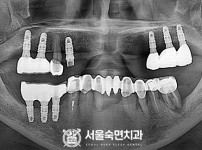

상악동거상술, 뼈이식 / 숙면임플란트 13개 - 오스템임플란트 (이*웅님)

상악동거상술 / 숙면임플란트 17개 - 오스템임플란트 (박*배님)

상악동거상술, 뼈이식 / 숙면임플란트 13개 - 오스템임플란트 (정*헌님)